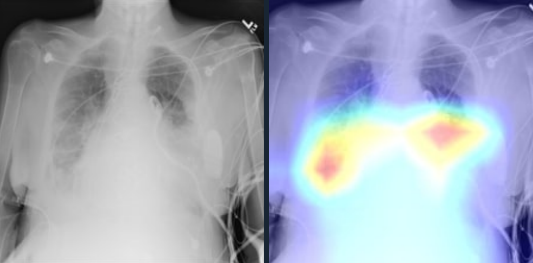

In Figure 3c the proposed model diagnoses the sample as a positive case for lung mass by detecting the right area. A lung mass is defined as an abnormal spot or area in the lungs larger than 3 centimeters (cm), about 1.5 inches, in size. Spots smaller than 3 cm in diameter are considered lung nodules. Finally, in Figure 3d, we have provided a positive case of Cardiomegaly, which is also known as an enlarged heart. In this case, the Grad-CAM mapping of our model shows that it was able to detect this condition by determining where the heart is located and especially, some edge parts of the heart.

Refer to caption

(c) Mass

Figure 3: Grad-CAM of our model for positive samples containing Consolidation, Atelectasis, Mass, or Cardiomegaly. For each sample, the original image is shown on the left and the Grad-CAM of the 3-layer headed SwinCheX is shown on the right.